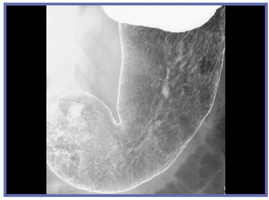

きれいに写るものも,きれいに写そうとしなければ写らないのであり,技師は良い画像を撮ることを意識しなければならない。バリウムをきれいに付着させる(図4),Cアームを活用して病変を正面からとらえる(図5)といったことにきちんと取り組むことが重要である。

![]() 図4 バリウムの付着が良好な画像 |